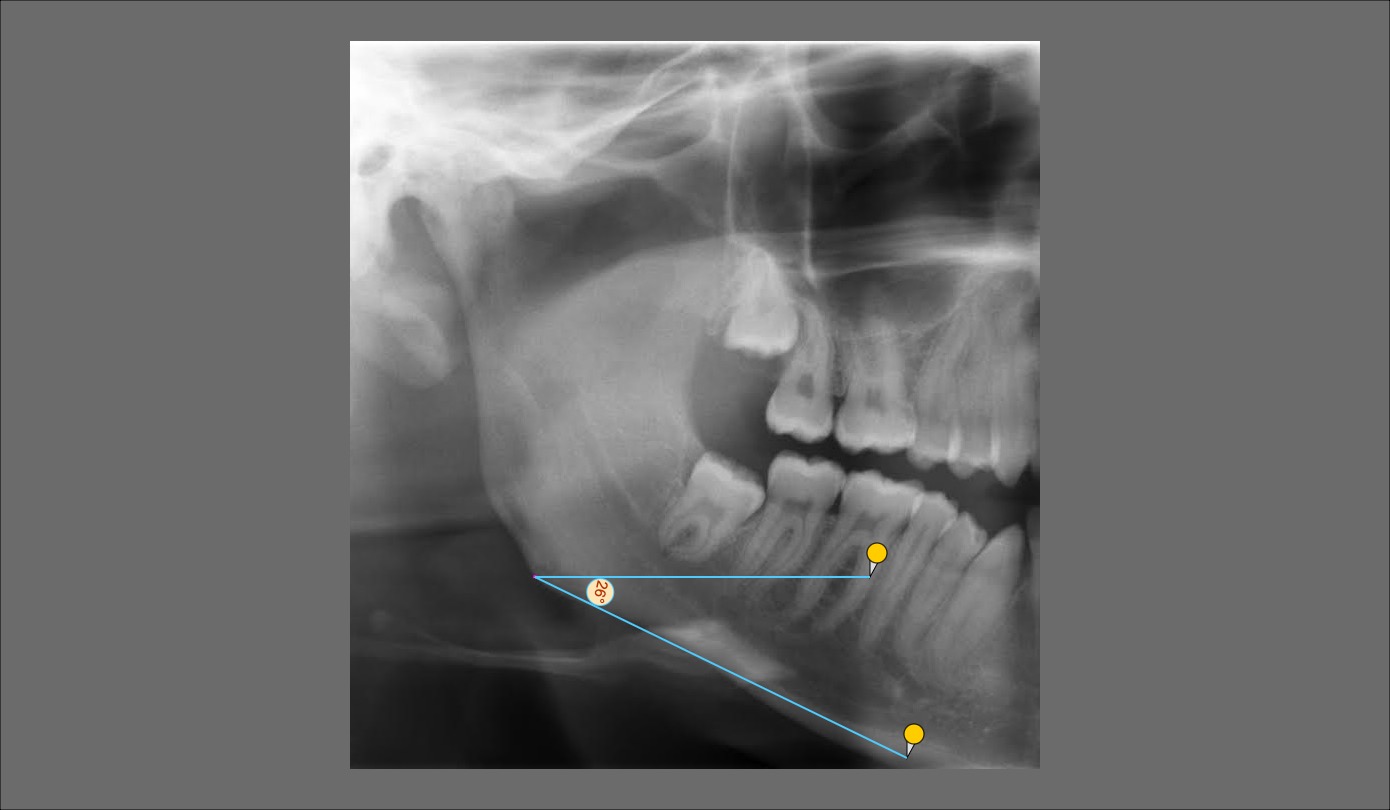

Sadly I don't have a full radiograph of my skull, but I do have one for my teeth. As you can see my ramus is pitifully short giving my a bad gonial angle. I'm having difficulty finding my occlusal plane as aforementioned problem but I think its around 15 die or take. as you can see the mandibular angle is around 26 degrees?! pretty crazy tbh, Maybe what I need is a bimax with a CCW? I was first thinking of getting implant for the ramus and wider jaw + paranasal implants due to a bit down grown maxilla.

Update: both occlusal plane and mandibular plane angles should be around 3 degrees lower, accounting for the open mouth in radiograph